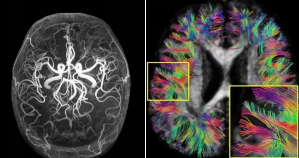

5.0T超高場高分辨成像效果(左:血管成像;右:腦神經(jīng)纖維束成像)

國際首創(chuàng)5.0T超高場全身磁共振